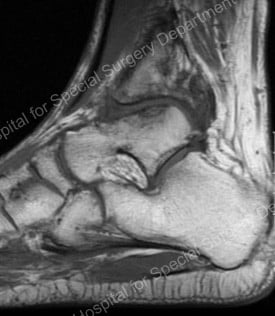

“Distraction” is achieved by literally pulling the joint surfaces apart. This allows the dense bone underneath the cartilage to soften, revascularize, and produce a healing response. Recent MRI studies of several patients have shown dramatic regenerative tissue growth on the arthritic bone surfaces one year after the procedure (Figure 4).

Figure 4: neo-cartilage or "new" cartilage (upper center of image)